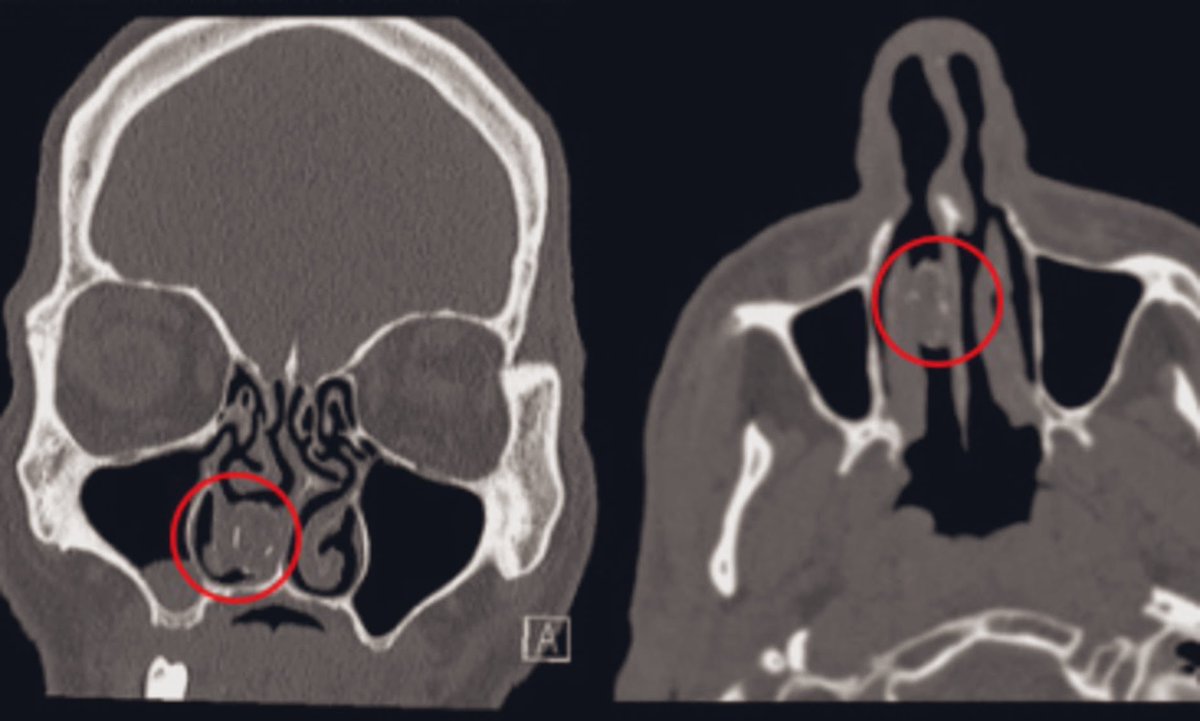

عانى المريض من الصداع و التهابات الجيوب الأنفية المزمنة وأعراض انسداد الأنف في السنوات التي أعقبت ذلك ..وعند زيارة المستشفى و عمل الاشعة المقطعية التي كشفت عن وجود انسداد ⬇️ تم ازالة الكبسولة ✔️ واستعاد المريض لصحته 👍🏼